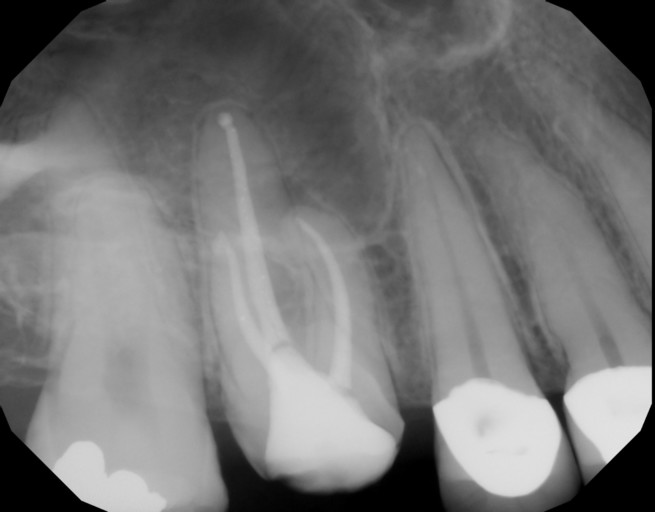

Had a root canal done almost a year ago but had the crown removed because food kept getting trapped underneath. It is tooth #29. It was omitting a bad smell from flossing the food out that kept getting trapped by the crown. Then I noticed on the xray theres a black space near the root. I asked the dental clinic where the root canal was done but seemed to avoid the question. Please see attached xray I did not want to put the permanent crown back on til I was certain but could not get a straight answer from my provider.

Unfortunately, I am unable to see the x-ray you submitted for tooth #29. However I do see the x-ray you submitted for the upper right tooth #3 which has a crown off and an existing root canal. Sometimes, a small black area around the apex of the root after a root canal can be a scar from the previous infection. It is hard to tell if it is a new infection, especially not being able to compare the pre-op and post-op x-rays. The large black space above the tooth is actually your sinus cavity. Any open space will appear more radiolucent (black) than for example, bone which is more dense. It is not a good idea to keep the crown off, the tooth is exposed and there is a risk of having a re-infection from the presence of bacteria. It is best to re-cement the crown even if it is with temporary cement to keep the tooth protected from bacteria, prevent the tooth from shifting and super erupting as well and worst case, fracture. These movements happen very quickly and will cause the crown to no longer fit the tooth. If the tooth were to fracture, there is a possibilty it would need to be extracted and a dental implant placed. It is better to be proactive in this situation.